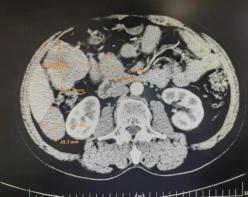

刘大爷2年前因被诊断胃肠道间质瘤(小肠)在外院手术治疗,一年后,腹部CT发现肿瘤复发(图1),经口服药物治疗,复查肿瘤较前缩小(图2),于是继续口服药物保守治疗,并未再来院复查。

近日,刘大爷因身体不适入住二一五医院肿瘤外二科,自觉胃部胀满不适、食量显著减少,仅能进食少量流质饮食,皮肤发黄,上腹部可触及一巨大肿物,CT提示肿物巨大,并已出现胆道及胃肠道压迫症状,药物治疗已无效,经多学科会诊(MDT)决定手术切除肿瘤。鉴于患者年龄大,手术风险高,贺伯伟主任团队制定详细周密的手术计划,历时3小时成功切除肿瘤。